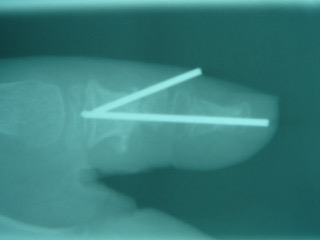

Figure 5 Case 2 post operative x-ray. Two K-wires were used to maintain reduction along with a bone graft